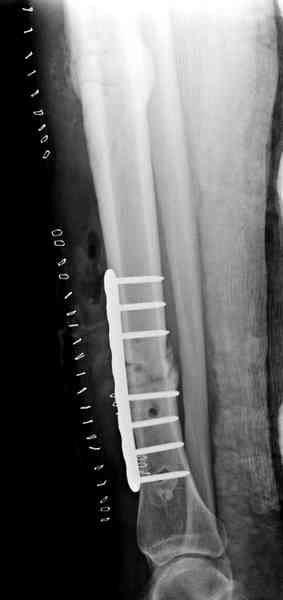

Недавно на нашей ежемесячной Morbidity&Mortality

conference мы разбирали похожий случай, ложный сустав большеберцовой кости после резекции опухоли.

Оперирован в военном госпитале с заменой сегмента

аллокостью большеберцовой кости и после демобилизации явился для постоянного наблюдения по месту жительства.

Наши имели проблему со сращением, пришлось им сделать динамизацию, дополнительную аутопластику.

Снимки представлены.